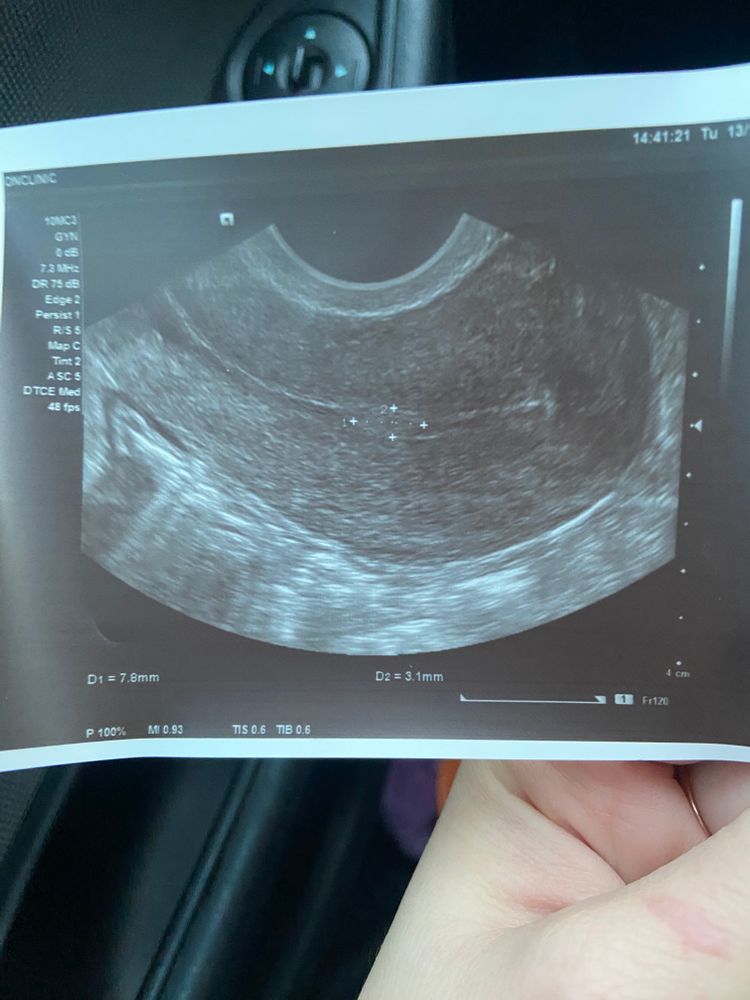

TSVETOCHEK, да, я решила пропить. Но думаю полип, там кровоток и сосуд есть а этом месте , а не просто бугристость

Татка, пропила норколут с 17 по 27 дц. Полип уменьшился, но полностью не ушёл. Теперь от 5,5 мм на 2,5 мм. Репродуктолог сказала, что он совсем маленький, поэтому не должен повлиять на зачатие. Будем пробовать беременеть)